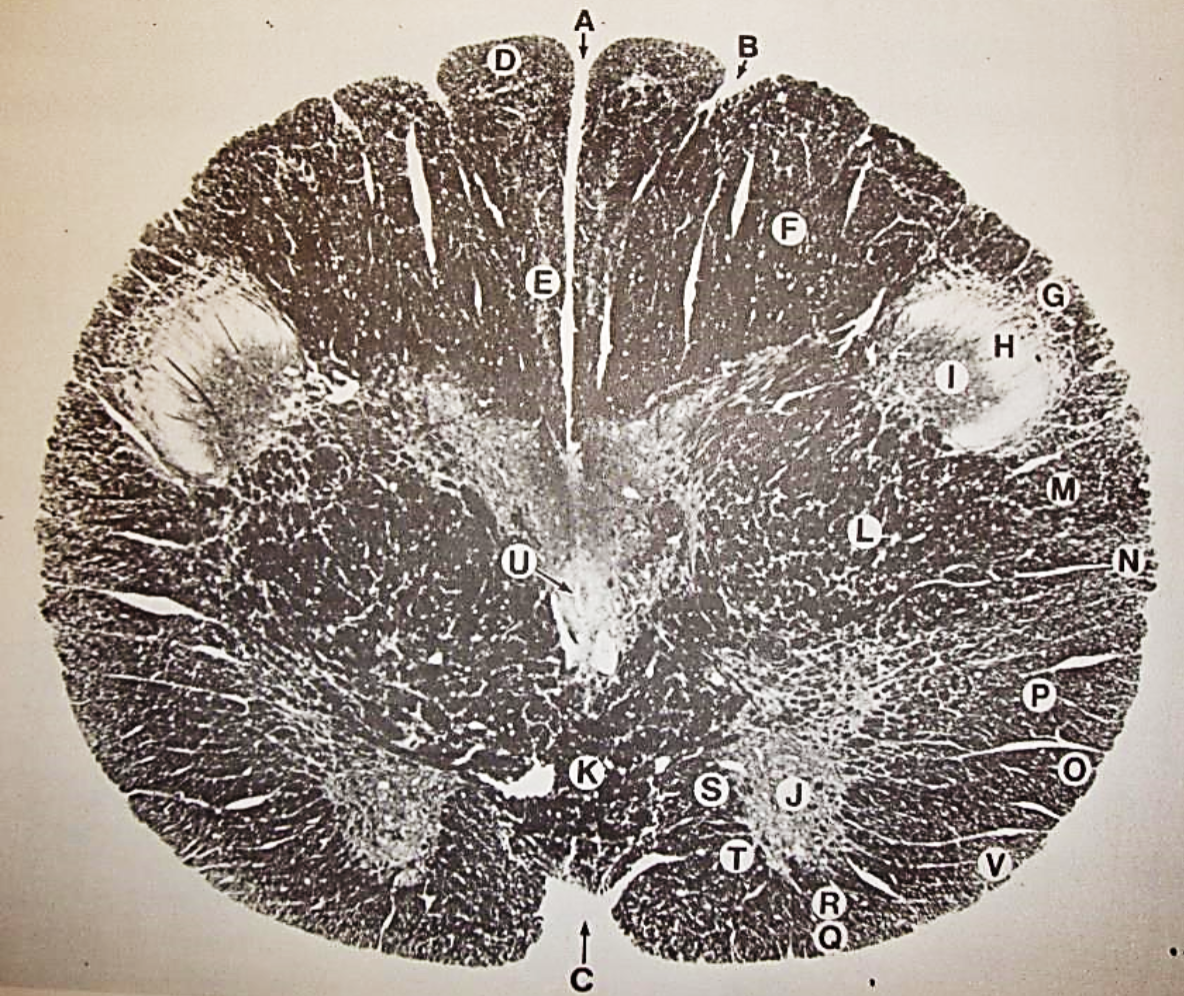

A

Fasciculus gracilis

B

gracile nucleus

C

fasciculus cuneatus

D

cuneate nucleus

E

spinal trigeminal tract

F+G collectively

spinal trigeminal nucleus

H

accessory nucleus

I

pyramidal decussation

J

rubrospinal tract

K

posterior spinocerebellar tract

L

anterior spinocerebellar tract

M

lateral spinothalamic tract

N

anterior spinothalamic tract

O

lateral vestibulospinal tract

P

medial longitudinal fasciculus

Q

tectospinal tract